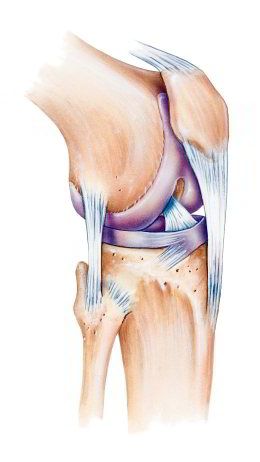

Kniescheibe mit Bändern,

Schema Seitenansicht Kniescheibe mit Bändern, Schema Seitenansicht [2] und von vorn [3]

-- die Kniescheibe ist eine etwas dreieckige Scheibe mit Wölbung zum Schutz des Knies

-- die Kniescheibe wird von Sehnen oben und unten gehalten, oben am Oberschenkelmuskel angesetzt, unten am Schienbein angesetzt

-- dank der Kniescheibe und den Sehnen kann man das Bein in leichter Weise strecken

-- die Rückseite der Kniescheibe hat eine Knorpelschicht für das Gleiten beim Beugen und Strecken des Beines

-- im Alter bildet sich die Knorpelschicht zurück, so beginnt oft eine Kniearthrose

-- Schäden an der Kniescheibe können sein: Fehlbildung, Bruch, Entzündung [web01]

-- die Kniescheibe bewegt sich in einer Art Rinne (Trochlea) des Oberschenkelknochens [web04,web05].

Knie mit Kniescheibe mit

Bändern, Vorderansicht

Hier ist die Rinne zwischen den beiden Wölbungen des Oberschenkelknochens. In dieser Rinne rutscht die Kniescheibe hin und her:

Die Kniescheibe gleitet in der Rinne

zwischen den beiden Wölbungen des Oberschenkelknochens

- Dr. Preis

Die Kniescheibe gleitet in der Rinne (lat.: Trochlea) zwischen den beiden Wölbungen des Oberschenkelknochens - Dr. Preis [6]